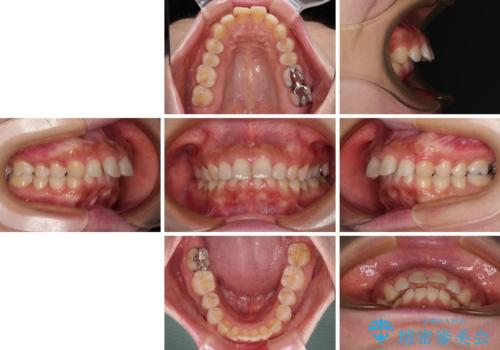

出っ歯を治したい ワイヤー装置での抜歯矯正

- 上の前歯が出っ歯と突出した口元を気にして来院された患者様です。

上顎歯列全体が前方に飛び出している印象であったので、上顎左右の第一小臼歯2本を抜歯し、ワイヤー装置にて抜歯矯正を行うこととしました。

骨格的に上顎が前方にあり、上顎のみの抜歯矯正のため、期間はかかることが予想されましたが、スムーズに移動してくれたおかげで、2年弱の短期間で終えることができました。